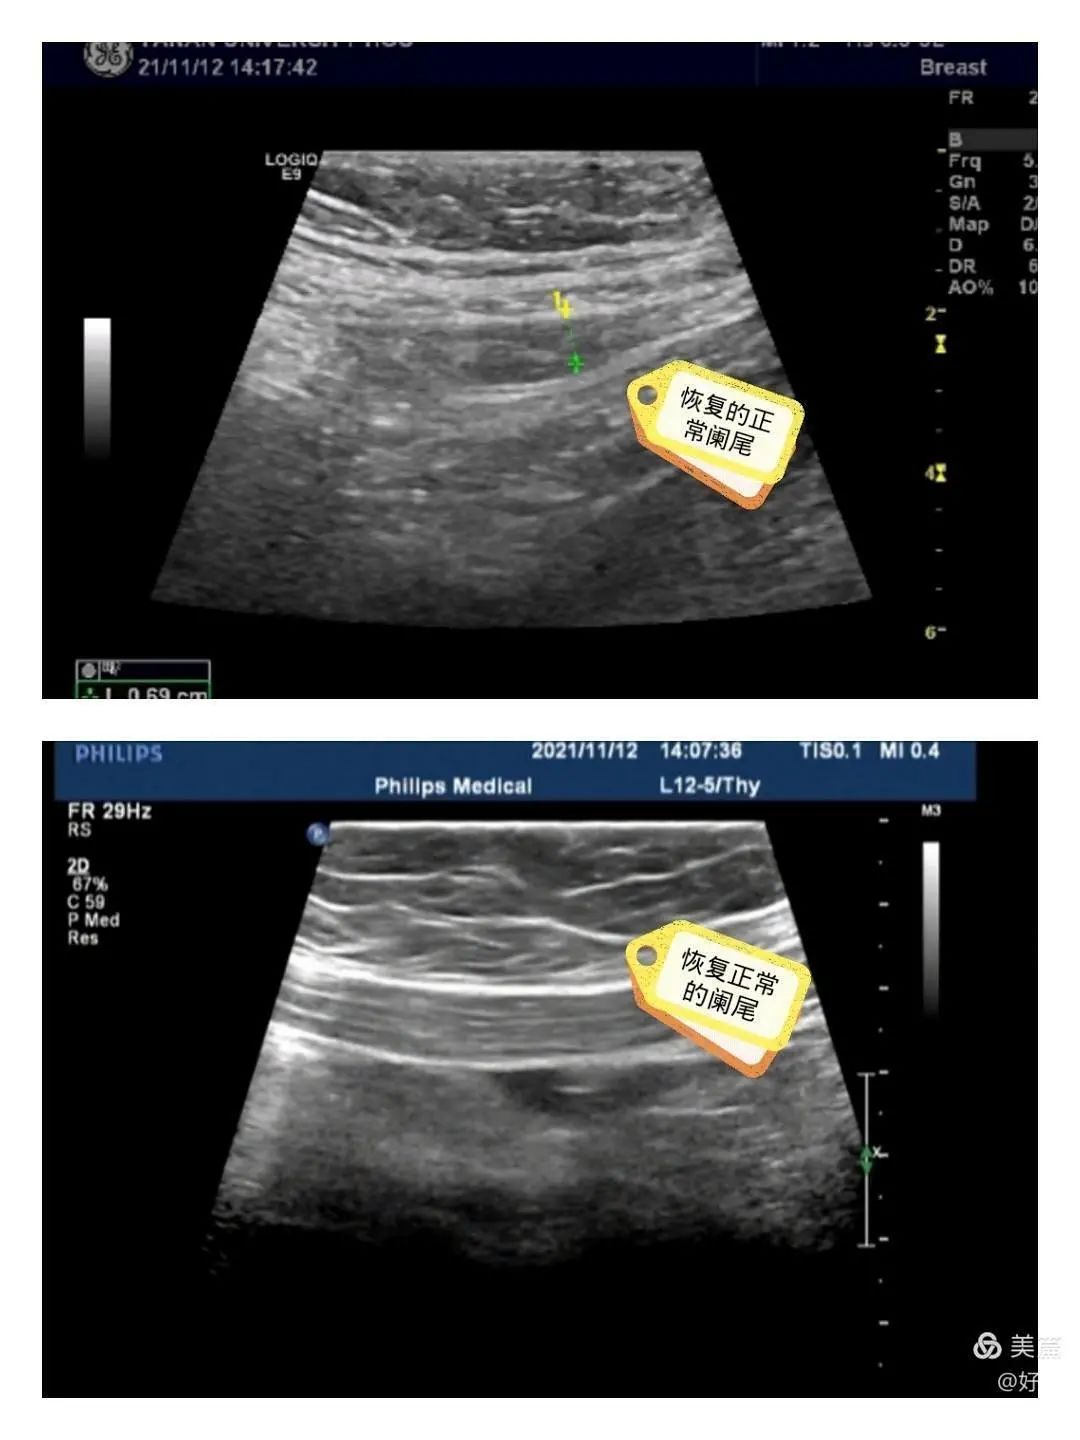

术后第二天复查感染指标下降,阑尾区 B 超示:未见明显阑尾肿胀。患儿 5 天后痊愈出院。